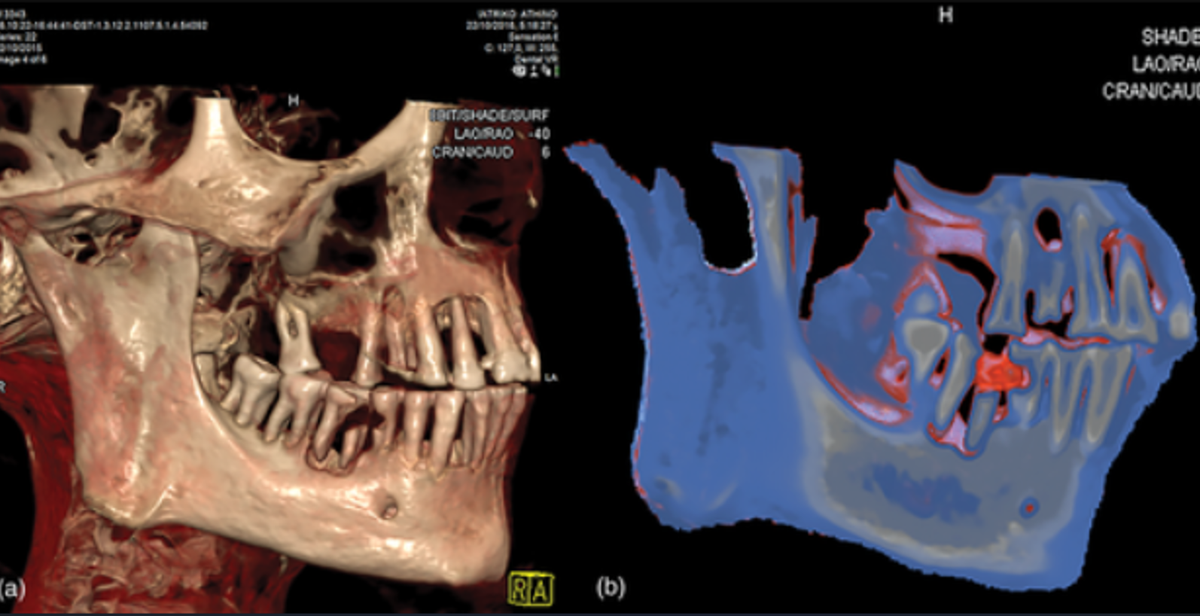

Để có được kết luận này, các chuyên gia đã sử dụng kỹ thuật chụp cắt lớp vi tính (CT) để mô tả đầy đủ về răng xác ướp Ai Cập. Ảnh: @Bảo tàng Khảo cổ học Quốc gia Athens.

Các nhà nghiên cứu đã tìm thấy một khoang xốp trong răng của xác ướp này chứa đầy vật liệu trám bảo vệ. Ảnh: @Bảo tàng Khảo cổ học Quốc gia Athens.

Tất nhiên, việc trám răng như vậy được thực hiện như một hình thức trị liệu chứ không phải là một phần của quá trình ướp xác. Ảnh: @Bảo tàng Khảo cổ học Quốc gia Athens.